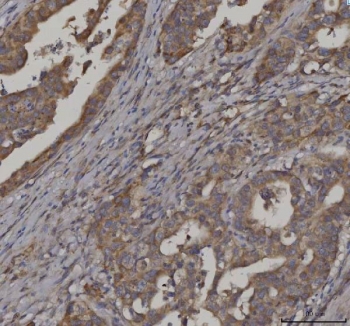

IHC staining of FFPE human colorectal adenocarcinoma tissue with FATP-3 antibody. HIER: boil tissue sections in pH8 EDTA for 20 min and allow to cool before testing.